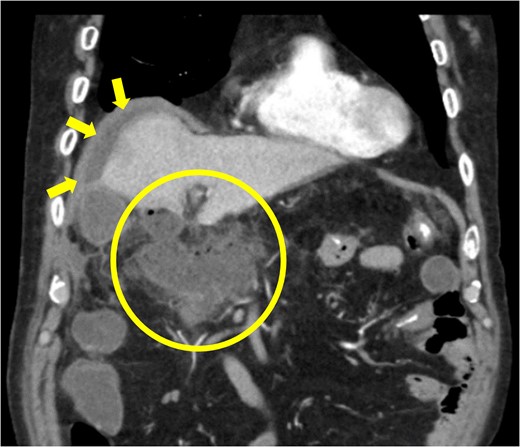

The amylase levels of drainage fluid and blood at postoperative day (POD) 1 (Ascites 6980 IU/dl, Serum 1123 IU/dl) and POD 3 (Ascites 673 IU/dl, Serum 487 IU/dl) revealed pancreatic fistula based on the criteria of International Study Group of Pancreatic Fistula [2]. After that, their results improved, and fluoroscopy showed no stenosis and leakage. Therefore, we removed all drains at POD 8, however the following day, the patient developed high fever. Plain CT revealed intraperitoneal fluid around subdiaphragmatic and duodenal stump (Fig. 3). We inserted a pig-tail drainage tube to the subdiaphragmatic space (Fig. 4). Since biliary fluid was discharged through the tube, we suspected duodenal leakage and started infusion of somatostatin analogs and antibiotics. At POD 13, the patient complained of whole abdominal pain with peritoneal signs. As the patient became hemodynamically unstable, we performed emergent laparotomy to lavage and insert multiple drainage tubes. Two perforation pinholes were identified in the anterior wall of the duodenum, near the stump. We resected the vulnerable duodenal stump including the perforation site and closed by Gambee’s method with unabsorbable 4–0 proline (Fig. 5). We inserted multiple drainage tubes (Fig. 6a): a C-tube from the cystic duct into the common bile duct to separate biliary juice and pancreatic juice, a dual drainage tube around the duodenal stump with continuous suction (Fig. 6b), a simple intraluminal drainage tube via the duodenum near the stump through a new skin incision on the left side of the abdomen for duodenal decompression, and a drainage tube into the rectovesical pouch. After the reoperation, we irrigated the cavity around the duodenal stump through each drain with saline. Since the contrast agent did not flow into the duodenum and the cavity around the duodenal stump gradually got smaller (Fig. 7), oral intake of fluid diet was initiated at POD 37. However, fistulography at POD 44 showed that the fistula of duodenal stump had relapsed (Fig. 8). Although we considered performing second reoperation for duodenal stump closure, due to the cavity around the duodenal stump was located, we continued conservative management and irrigation via drainage tubes. Fistulography demonstrated no leakage from the duodenal stump at POD 56, and the patient discharged at POD 59.

Primary drainage for duodenal fistula. As percutaneous approach, we inserted a pig-tail drainage tube to subdiaphragmatic space (asterisk) using X-ray fluoroscopy.